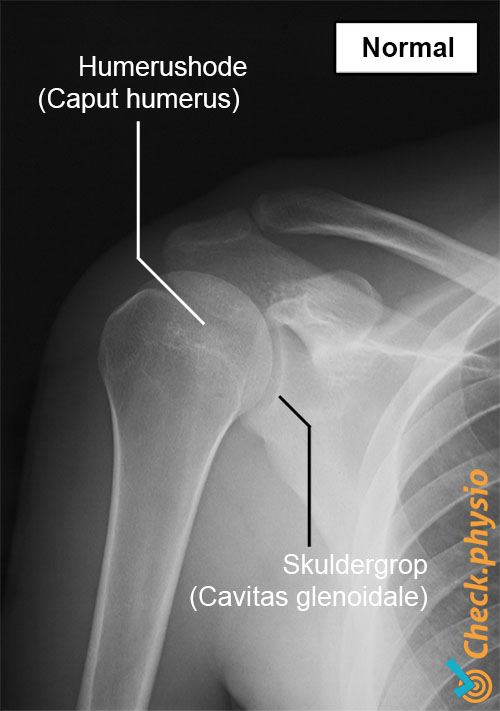

Skulderen består blant annet av en leddkule og en leddpanne. Leddpannen i skulderen er i realiteten kun en liten fordypning i forhold til den mye større skulderkulen. Dette gir skulderen stor bevegelighet, men gjør også leddet ustabilt. Denne ustabiliteten kompenseres i stor grad av musklene i skulderen, og i mindre grad av leddbåndene rundt leddet.

Ved mistanke om at skulderen er ute av ledd, gjøres videre radiologisk undersøkelse. Et røntgenbilde viser retningen på luksasjonen og om det foreligger et brudd. Det bør også undersøkes om muskler eller leddkapsel er skadet.